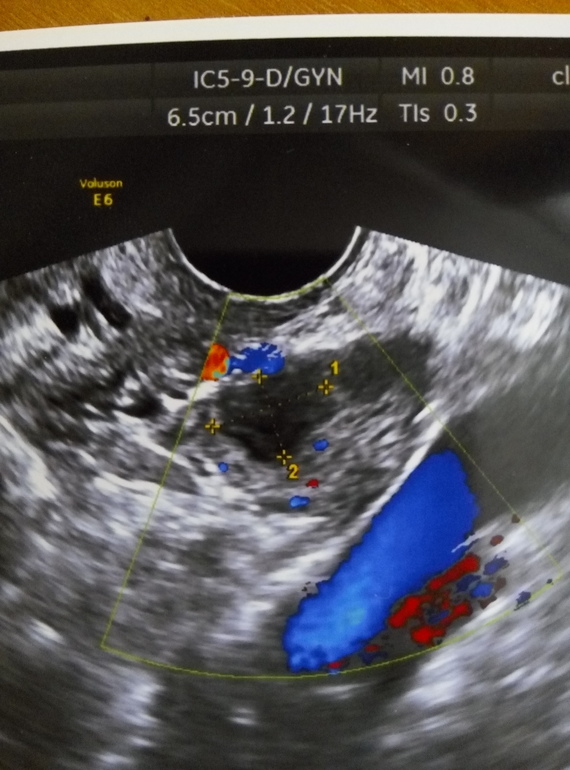

Узи. Эндометриозная киста.

ФолликулометрияДевочки, кто разбирается в узи. Посмотрите пожалуйста,это похоже на эндометриозную кисту? в левом Я

Это кистозное желтое тело, эндометриоидные кисты выглядят иначе, внутри их взвесь. Но на УЗИ повторно сходите обязательно после менструации

похоже на желтое тело, края неровные.

эндометриальные кисты выглядят иначе, они круглые как фолликул и фон зернисто-серый.

не у тебя точно жт, только что-то без кровотока.

в ЛЯ спавший фолликул 10 на 13 и гипоэхогенное образование 13,4 на 9,4 Подозрение на эндометриоидную кисту